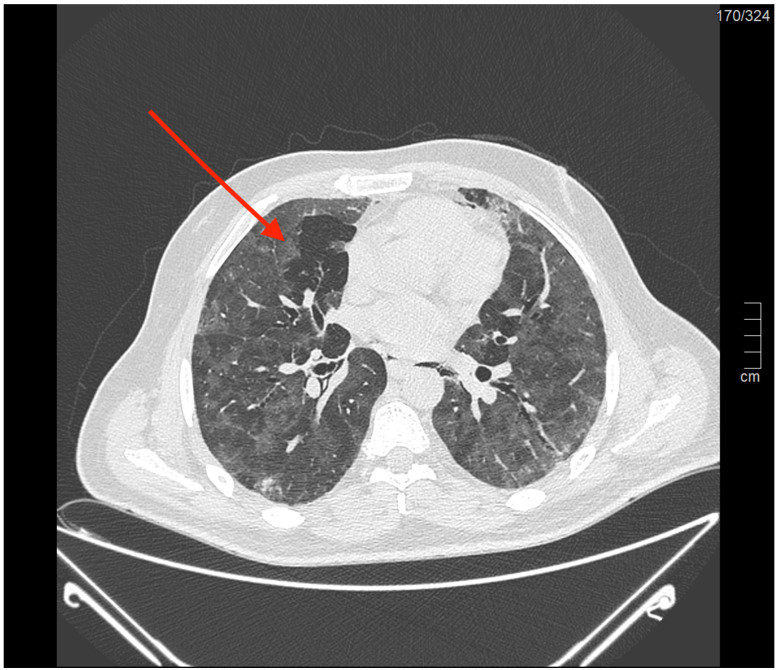

背景:麦克林效应最近在COVID-19 ARDS人群中显示出对气压创伤的高阳性预测价值。然而,关于没有SARS-CoV-2感染的ARDS人群的证据较少。我们的目的是分析COVID-19和非COVID-19 ARDS受试者,以评估Macklin效应在预测两组气压损伤发展方面的敏感性和特异性。方法:回顾性分析2018年1月至2022年11月在本中心收治的ARDS患者。经验丰富的放射科医生在胸部计算机断层扫描中检查了麦克林效应的存在。然后根据麦克林效应的存在与否将受试者分为两组,以评估其对气压创伤的预测能力。最后,我们分析了麦克林效应和气压创伤对重症监护病房和住院死亡率的影响。结果:我们分析了225例患者;在44名受试者中观察到麦克林效应。在我们的队列中,麦克林效应在预测气压损伤方面的敏感性为44.6%,特异性为90.6%。在排除COVID-19 ARDS病例后,麦克林效应的敏感性为34.7%,特异性为93.6%。尽管如此,在我们的人群中,麦克林效应的存在或气压创伤的发生并未导致ICU或住院死亡率的增加。结论:我们的分析强调,麦克林效应在预测气压创伤方面具有高特异性,但敏感性较低;此外,气压创伤的发生并不影响死亡率,这可能是由于排除了轻度至中度ARDS和纳入了大量ECMO受者。最后,麦克林效应在ARDS早期出现,可能作为肺衰弱的早期指标,可能成为转介到ARDS高级治疗中心的附加标准。

Background: The Macklin effect recently demonstrated a high positive predictive value for barotrauma in the COVID-19 ARDS population. However, there was less evidence available regarding the ARDS population without SARS-CoV-2 infection. We aim to analyze COVID-19 and non-COVID-19 ARDS subjects to assess the sensitivity and specificity of the Macklin effect in predicting the development of barotrauma in both groups. Methods: We retrospectively analyzed subjects with ARDS admitted to our center from January 2018 to November 2022. Experienced radiologists examined the presence of the Macklin effect on chest computed tomography scans. Subjects were then divided into two groups based on the presence or absence of the Macklin effect to assess its predictive power regarding barotrauma. Finally, we analyzed the impact of the Macklin effect and barotrauma on Intensive Care Unit and in-hospital mortality. Results: We analyzed 225 patients; the Macklin effect was observed in 44 subjects. In our cohort, the Macklin effect exhibited a sensitivity of 44.6% and a specificity of 90.6% in predicting barotrauma. After excluding the COVID-19 ARDS cases, the Macklin effect showed a sensitivity of 34.7% and a specificity of 93.6%. Nonetheless, in our population, the presence of the Macklin effect or the occurrence of barotrauma did not lead to increased ICU or in-hospital mortality. Conclusions: Our analysis highlighted that the Macklin effect demonstrates high specificity in predicting barotrauma but a low sensitivity; moreover, the development of barotrauma did not impact mortality, possibly due to the exclusion of mild to moderate ARDS and the inclusion of a significant number of ECMO recipients. Finally, the Macklin effect appears early during ARDS and may serve as an early indicator of lung frailty, potentially becoming an additional criterion for referral to centers for advanced ARDS treatment.